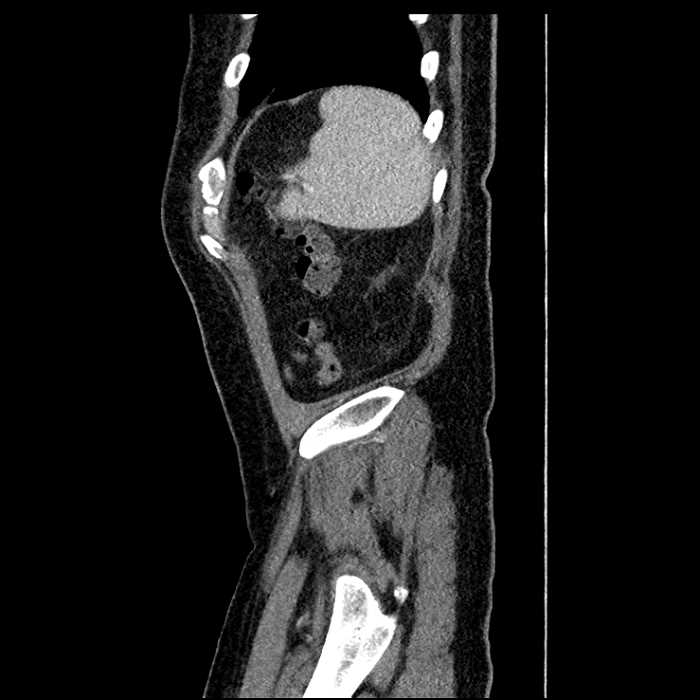

• Large fluid density structure in hepatic segments 7 and 8 measuring 10 x 7 x 7 cm with internal septation and circumferential ill-defined low density compatible with edema

• Peripherally enhancing subcapsular collections along the anterior margin of the left hepatic lobe measuring 3 x 1 cm and 2 x 1 cm

• Clearly marginated fluid density structure in segment 7 and several other scattered tiny hypodensities, which likely represent cysts

Acute sigmoid diverticulitis complicated by a small contained perforation and a large abscess in the right hepatic lobe. Additional small subcapsular abscesses along the anterior margin of the left hepatic lobe.

• The classic CT imaging appearance is a double target sign with internal low density surrounded by an internal enhancing rim (capsule) and a low density external rim (edema)

Hepatic abscess showing the double target sign with low density internally surrounded by a thin inner enhancing rim (red arrow) and ill-defined outer low density rim (yellow arrow). Blue arrow indicates an internal septation. Red arrows: additional smaller subcapsular abscesses. Red arrow: focal contained perforation associated with diverticulitis.